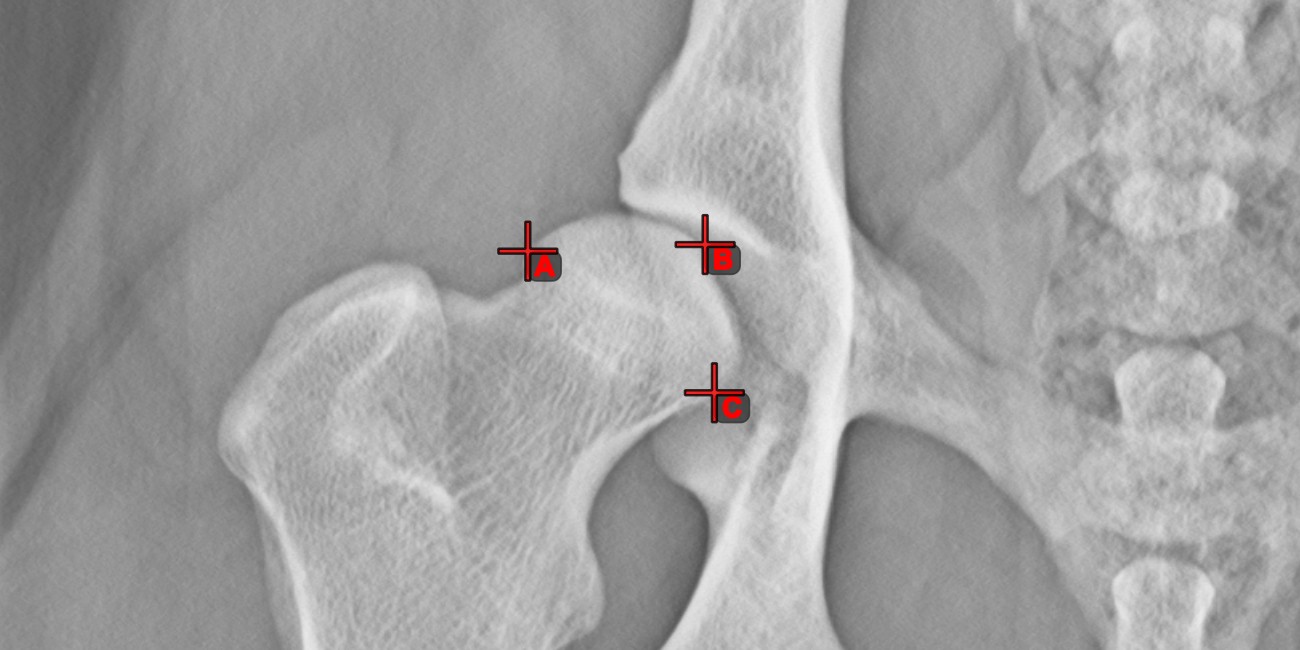

Szög 3 pontból¶

A Szög 3 pontból eszköz egyszerű és hatékony módja annak, hogy egy szöget mindössze három pont alapján számítson ki.

Kezdje az eszköz kiválasztásával a bal oldali eszköztárból, és rendelje hozzá az egyik elérhető egérgombhoz. Helyezze el a szög kezdeti oldalának kezdőpontját, a csúcsot és a szög végoldalának végpontját, vagy válassza ki a pontokat a jelenetből. A szög oldalai automatikusan létrejönnek, így a vonalak közötti szög kiszámításra kerül.

Módosítsa a három pont helyzetét a szög ívének megváltoztatásához az Elem kiválasztása/mozgatása eszközzel.